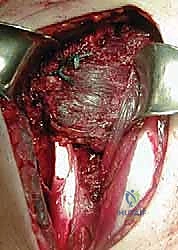

الخطوة الثانية: النهج الجراحي واستكشاف المفصل

يتم عمل شق جراحي أمامي (Deltopectoral Approach) للوصول إلى مفصل الكتف. يقوم الدكتور هطيف أولاً بتقييم حالة الكفة المدورة التالفة والتأكد من عدم قابليتها للإصلاح، مع تنظيف المفصل من أي أنسجة ملتهبة أو التصاقات باستخدام أدوات دقيقة.

الخطوة الثالثة: حصاد وتر العضلة الصدرية الكبرى

هذه هي الخطوة الأكثر دقة. يقوم البروفيسور هطيف بتحديد الجزء العلوي (الترقوي) أو الجزء السفلي (القصي) من العضلة الصدرية الكبرى، بناءً على التقنية الأنسب للمريض. يتم فصل الوتر بعناية فائقة من مكان ارتكازه على عظمة العضد، مع الحفاظ التام على العصب المغذي (Pectoral Nerves) والأوعية الدموية لضمان بقاء العضلة حية وقادرة على الانقباض.

الخطوة الرابعة: تحضير العظم (Lesser Tuberosity)

يتم تحضير المنطقة العظمية في مقدمة رأس عظمة العضد (مكان الارتكاز الأصلي لعضلة تحت الكتف التالفة). يتم تقشير العظم بلطف لتحفيز النزيف الدقيق، مما يساعد على سرعة التئام الوتر المنقول مع العظم لاحقاً.